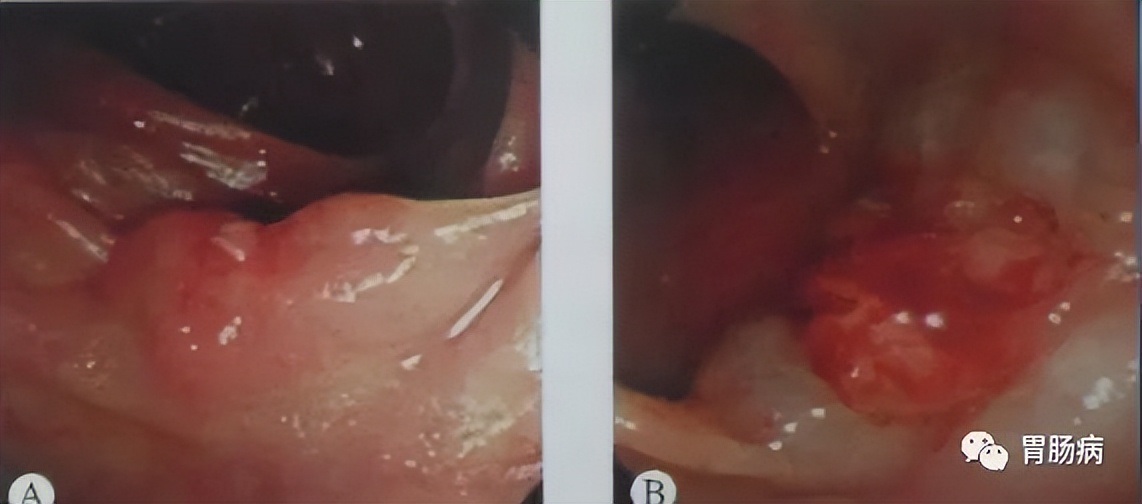

五、ESD的基本步骤

基本步骤如下图所示:

下面详细讲解:

1.标记:

应用针形切开刀或APC于病灶边缘0.5-1.0cm进行电凝标记。

2.抬起:

于病灶边缘标记点外侧进行多点粘膜下注射,每点约2ml,可重复注射,直至病变明显抬起。上消化道黏膜下注射原则先肛侧后口侧。下消化道黏膜下注射先口侧后肛侧。

3.切缘:

应用针形切开刀、HOOK刀、IT刀沿病灶边缘标记点切开粘膜。缘切开时会引起出血.一旦出血要及时处理,可用治疗器械电凝止血或热活检钳电凝止血;边缘切开过深时,会造成切开部位穿孔,可应用金属夹夹闭,不必终止ESD治疗。

4.剥离:

应用IT刀或HOOK刀沿切缘对病变黏膜下层进行剥离,切除病变以大头针固定后送病理检验。

5.创面处理:

完整剥离病灶后要对创面进行处理,对出血点要进行止血:

面积较大或侵犯层次较深的创面,要应用金属夹夹闭,防止术后穿孔的发生。